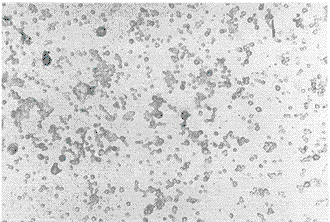

2.4 细胞肺癌抗原及B7分子的表达 S-P免疫细胞化学显示ALA9702细胞仅表达肺癌抗原,不表达B7分子,而FLB2C细胞则既表达肺癌抗原、又表达B7分子,B7分子主要分布在细胞膜及细胞浆。FLB2C细胞表达B7结果显示见图2。

图2 FLB2C细胞Mab B7 S-P免疫细胞化学染色×40|96x}qx, 百拇医药

Fig2 Mab B7 S-P immunocytochemistry of FLB2C cells|96x}qx, 百拇医药